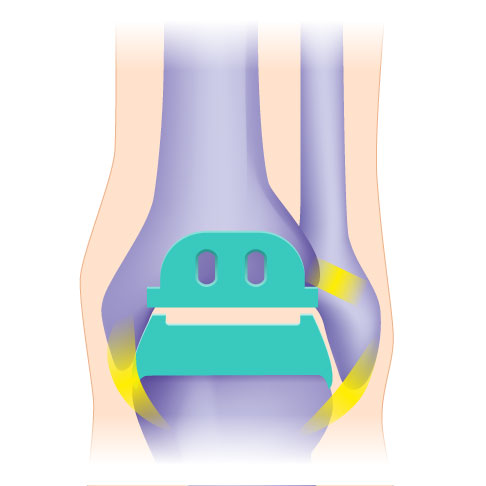

Die knochensparenden 3-Komponenten-Prothesen für das obere Sprunggelenk (OSG-TEP) bestehen aus mehreren Komponenten. Die Teile der Sprunggelenksprothese stehen frei übereinander, sind zueinander beweglich und überdecken die geschädigten Gelenkabschnitte (blau). Die Implantate wachsen an den Gelenkflächen in die Knochenoberfläche ein. Geführt werden die Anteile der Sprunggelenksprothese von den vorhandenen Sehnen, Muskeln und Bändern. Eine intakte Beinachse sowie optimale Fußstellung und funktionierende Bänder sind unverzichtbar für eine haltbare Sprunggelenksprothese. © Gelenk-Klinik

Die Drei-Komponenten-Prothese ist im Vergleich zur Zwei-Komponenten-Prothese flexibler. Sie unterstützt die natürliche Biomechanik des Sprunggelenks, weil sie in alle Richtungen beweglich sind. Die Drei-Komponenten-Prothese kann bei stabilen und korrekten Achsverhältnissen knochensparend eingesetzt werden.

Die Zwei-Komponenten-Prothese erreicht eine höhere Stabilität, weil das Kunststoffinlay stabil im Schienbein fixiert wird. Diese Prothese eignet sich besonders bei einem sehr instabilen Sprunggelenk. Da der Spezialist das Inlay in höherer Lage im Knochen befestigt, muss er bei diesem Eingriff mehr Knochengewebe entfernen.

Eine günstige Voraussetzung für den Einsatz eines künstlichen Sprunggelenkes ist ein stabiler Bandapparat. Weil die 3-Komponenten-Prothese des Sprunggelenks keine Kopplung zwischen den Gelenkflächen hat, sondern lediglich einen beweglichen Polyethylenkern, gewährleisten die Muskeln, Sehnen und Bänder ihre Stabilität. Das Kunstgelenk ist ebenso wie das natürliche Gelenk auf die Führung durch die Weichteile angewiesen.

Bei geringerer Stabilität der Bänder ist dagegen die 2-Komponenten-Sprunggelenksprothese eine Option. Sie bietet durch die feste Verankerung des fixierten Inlays im Schienbein eine höhere Stabilität. Nichtsdestotrotz ist auch vor ihrer Implantation erforderlich, Fehlstellungen und Bandschäden zu erkennen und gegebenenfalls zu korrigieren - denn auch eine 2-Komponenten-Prothese benötigt einen idealen Sitz und eine gute Führung